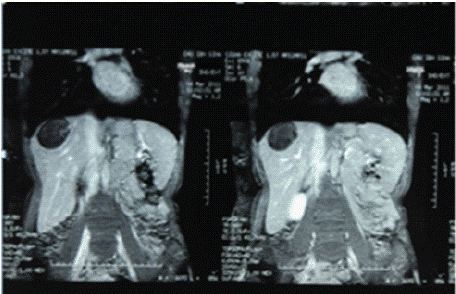

Ultrasound of the right liver (anterior sector) revealed a heterogeneous cystic image with a thin wall, suggestive of a type IV hydatid cyst. Abdominal CT confirmed a multiloculated cystic lesion containing fatty, calcified, and fluid components, suggestive of a hepatic teratoma. An MRI scan further supported the diagnosis, showing a grossly oval lesion in the hepatic dome measuring 57 × 48 mm. The lesion contained a fluid level with a supernatant displaying T1 hypersignal, T2 hyposignal, and a dependent portion in T1 and T2 isosignal, without enhancement after gadolinium injection — findings suggestive of a modified hydatid cyst.

Figure 1: Axial abdominal MRI C+.